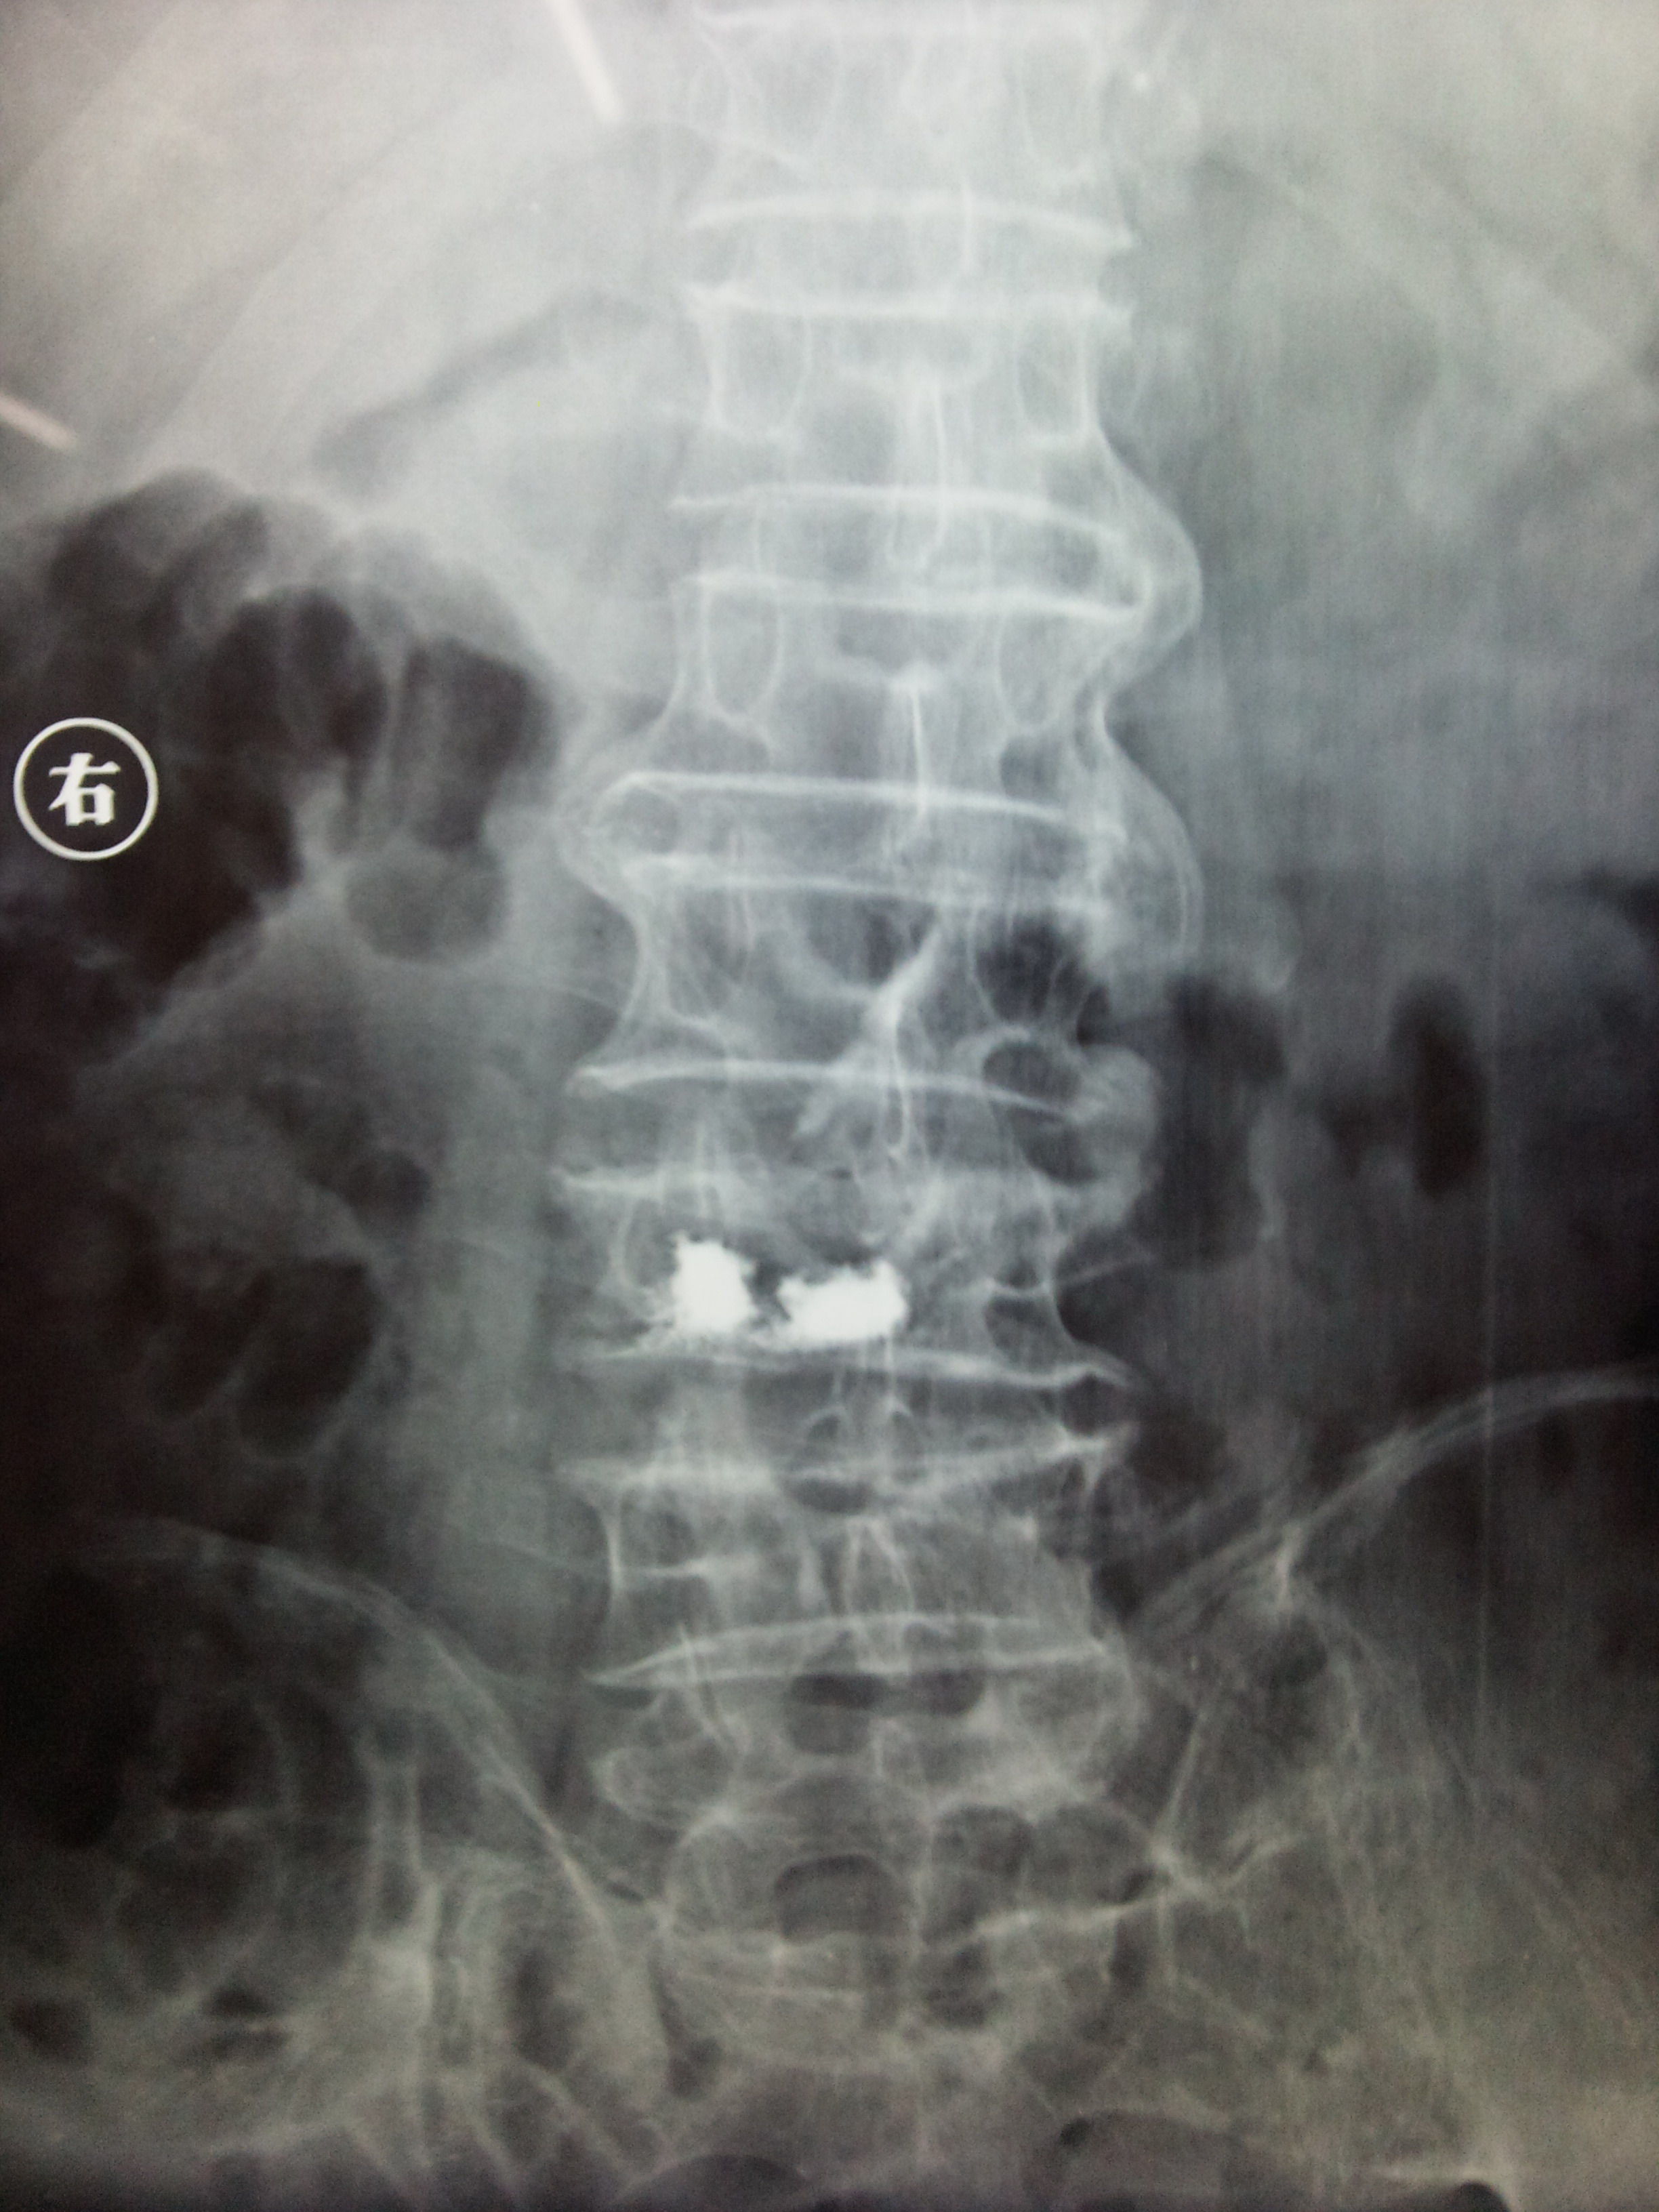

患者,男性,79岁,无明显外伤史致腰痛一个月为主诉入院。入院查体:一般情况好,腰椎活动明显受限,转侧困难,双下肢感觉运动无异常,大小便正常。入院腰椎正侧位片示:第三腰椎压缩性骨折。腰椎MRI示:第三腰椎压缩性骨折(新鲜)。见下图。